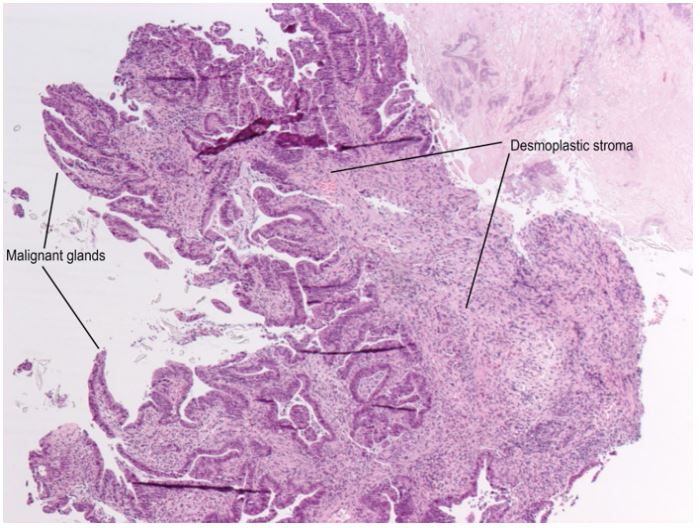

A 70-year old female was referred to the emergency department of a tertiary hospital by her general practitioner with a sixmonth history of lethargy, six-kilogram weight loss and vague right sided abdominal pain. She denied vomiting, altered bowel habit or rectal bleeding. Her relevant surgical history included cholecystectomy and thyroidectomy. There was no family history of colorectal cancer. Pertinent examination findings included a soft, non-distended abdomen with a large non-mobile palpable mass in the right upper quadrant. Her blood profile included leukocytosis (12.9 x109 /L), anaemia (Hb 79 g/L), normal bilirubin and mildly deranged liver function tests. Furthermore, she had a markedly raised CA 19.9 (5506 kU/L) and CEA (462.1 microg/L). She was admitted for a blood transfusion and further investigations. A triple phase computed tomography scan of the chest, abdomen and pelvis revealed an 11x10x10.5 cm hepatic flexure mass with invasion into the right hepatic lobe (Figure 1). Surprisingly, there was no evidence of colonic obstruction, nor distant metastatic disease. A colonoscopy demonstrated a large circumferential, fungating and partially obstructing mass extending into the ascending colon (Figure 2). Biopsy confirmed a poorly differentiated invasive adenocarcinoma (Figure 3). Following discussion at a multi-disciplinary surgical oncology meeting, she proceeded to an ileo-colonic bypass with planned adjuvant chemotherapy. Intra-operatively, the mass was invading the liver, with small amounts of ascites and no peritoneal metastasis. Proximal small and large bowel were of normal caliber. An ileo-colic side-to-side anastomosis was performed using the distal ileum and mid transverse colon. The patient made an uneventful recovery and was discharged day four post operatively with medical oncology follow up.

Figure 3: Histopathology of the colonic biopsy showing malignant glands of the adenocarcinoma invading into a desmoplastic stroma (H&E stain, x50 magnification).